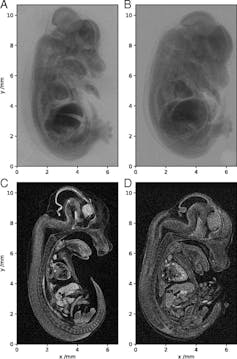

Besides these two advantages, our accelerator can perform certain new functions that existing accelerators cannot. For instance, plasma-based accelerators can provide detailed X-rays of biological samples with far greater clarity than those that exist today. By providing a better image of the inside of a human body, could help doctors find cancer at a much earlier stage, dramatically increasing the chance of successfully treating the illness.